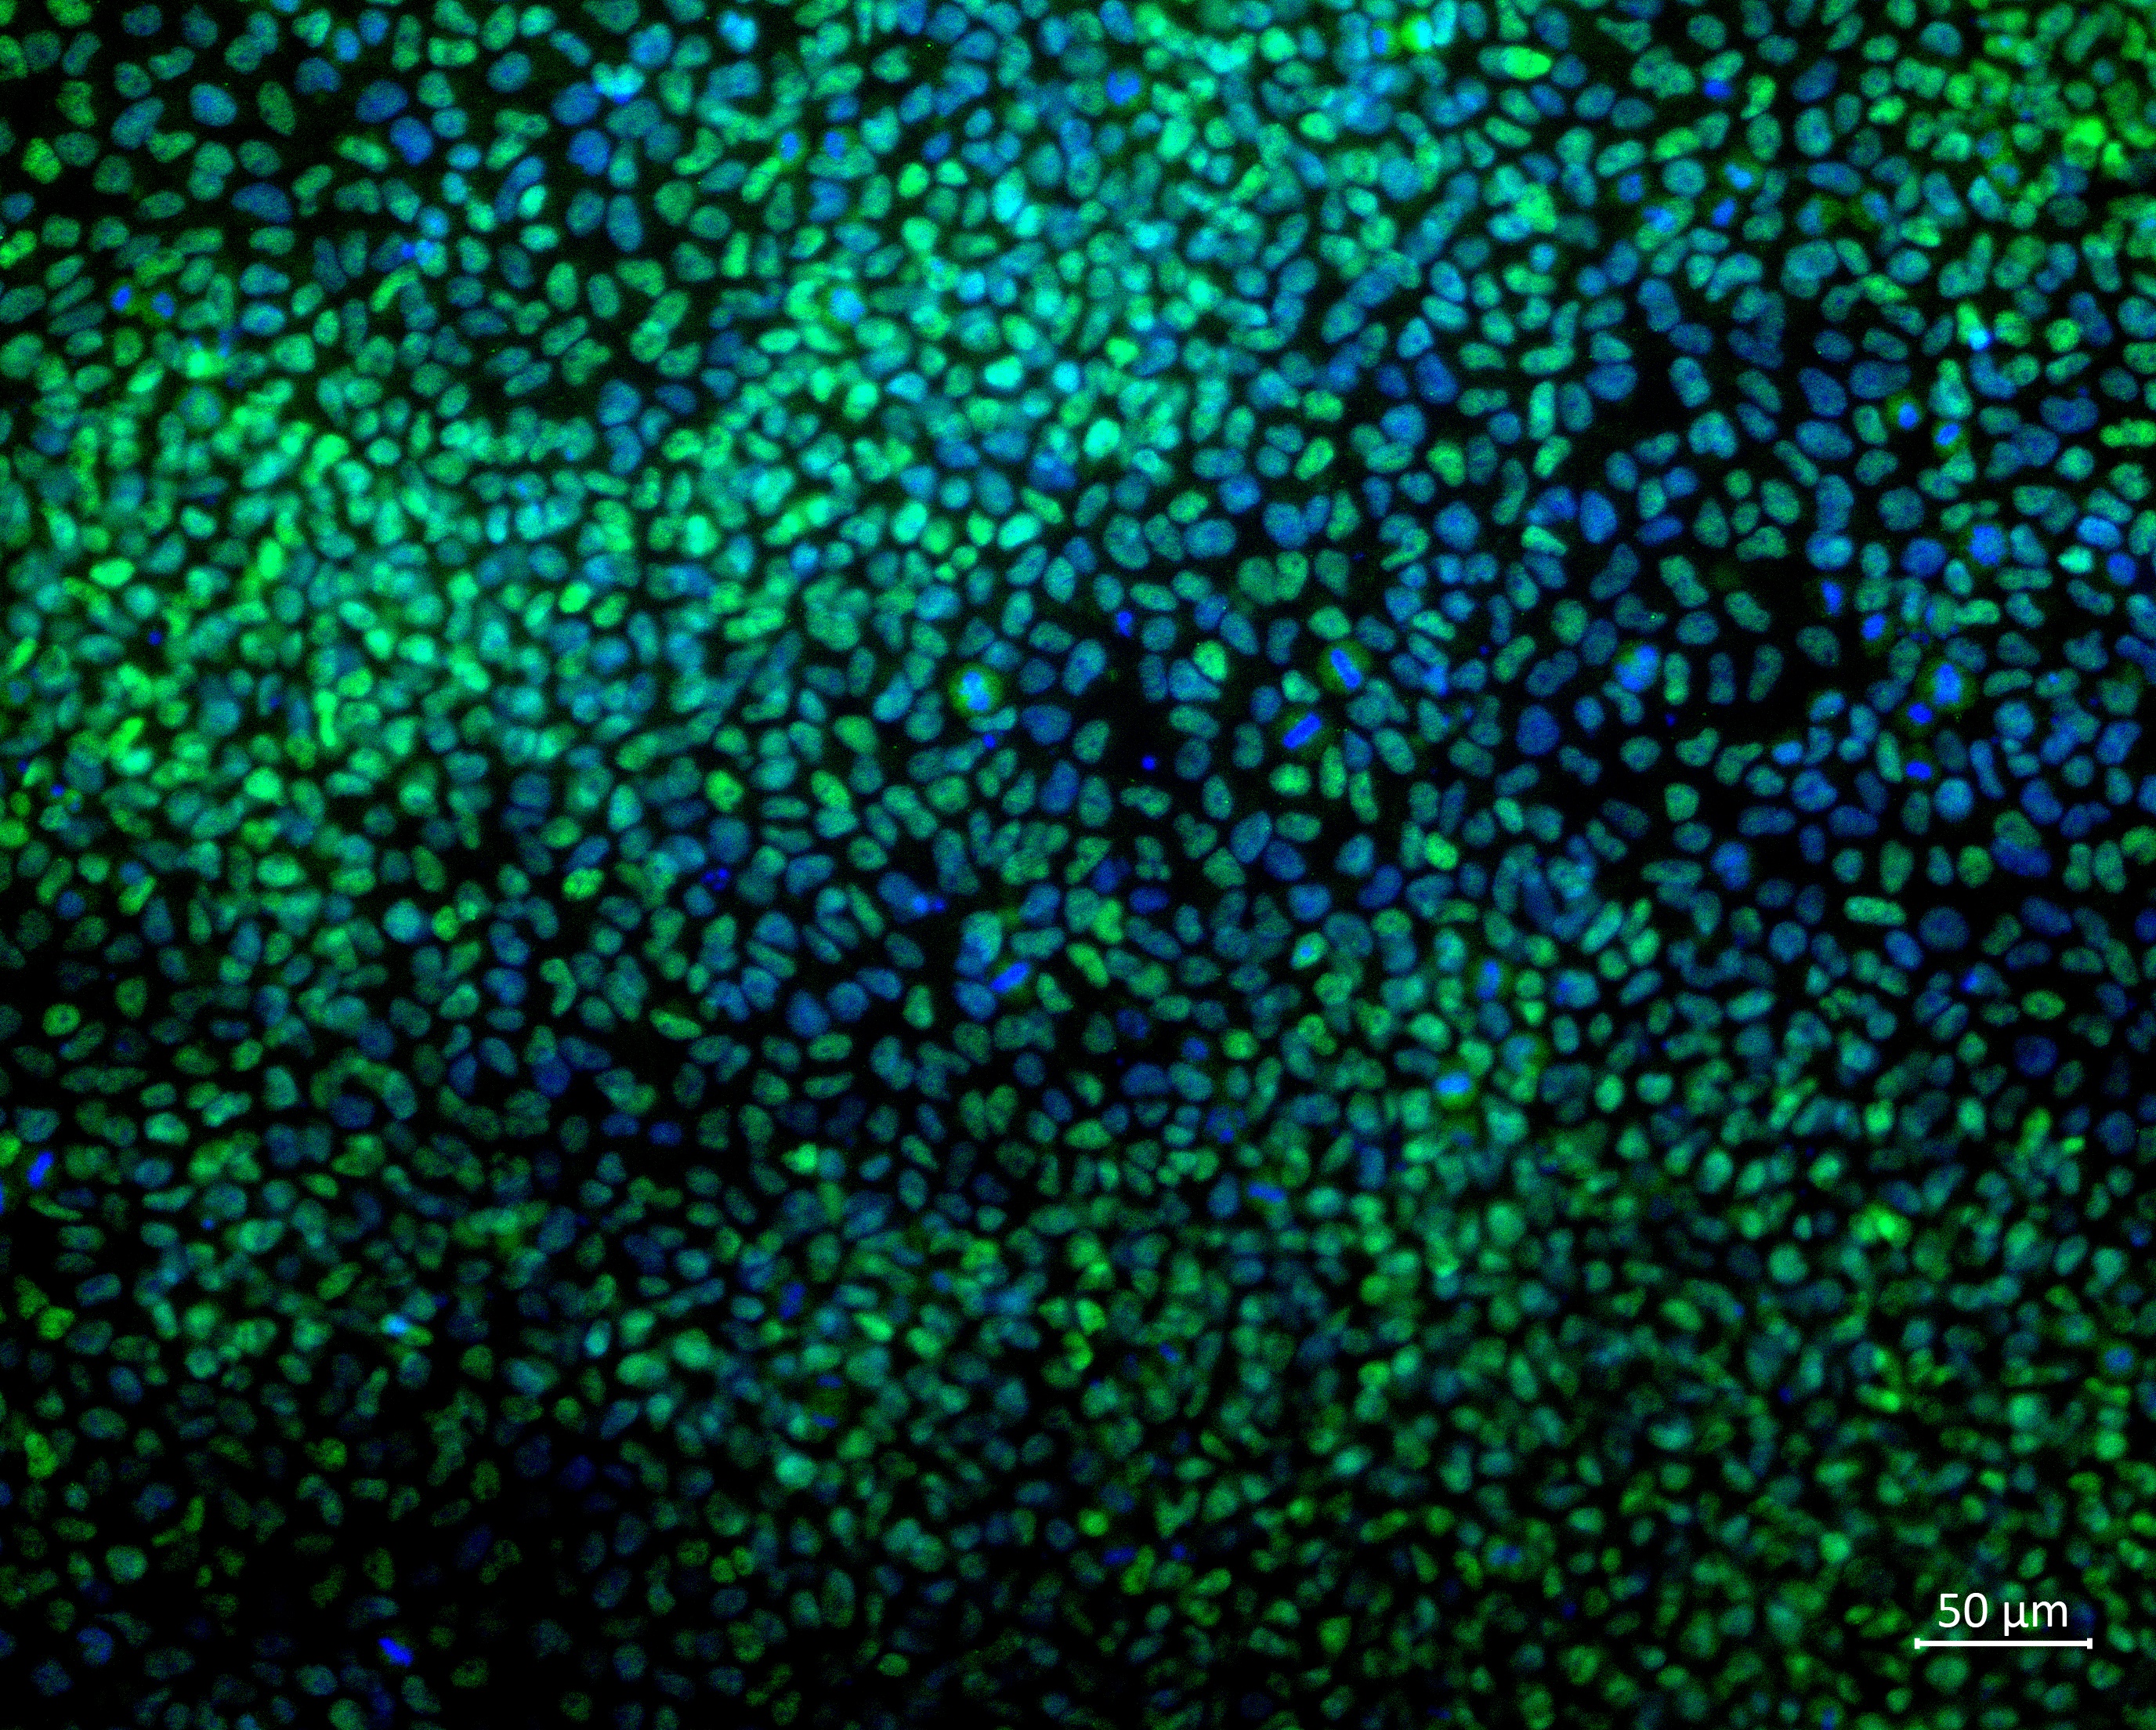

Analysis of Undifferentiated Cells

| Marker | Expressed | Immunostaining | RT-PCR | Flow Cytometry | Enzymatic Assay | Expression Profiles |

| POU5F1 (OCT-4) |

Yes |

| SOX2 |

| NANOG |

| SSEA-4 |